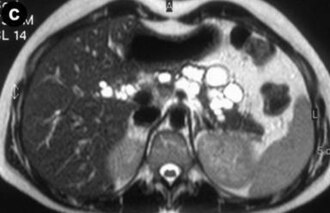

Liver phantom with multiple focal lesions including hemangioma, hepatocellular carcinoma, cyst, and metastasis for...